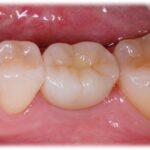

治療後

2ヵ月で最終的なセラミック冠を装着しています。下顎の奥歯に関しては6㎜という短い長さのインプラントでも十分長持ちすることが今では分かっています。

当院ではなるべく手術後の痛みや腫れの少ない、治療期間の短い方法を考えて取り組んでいます。